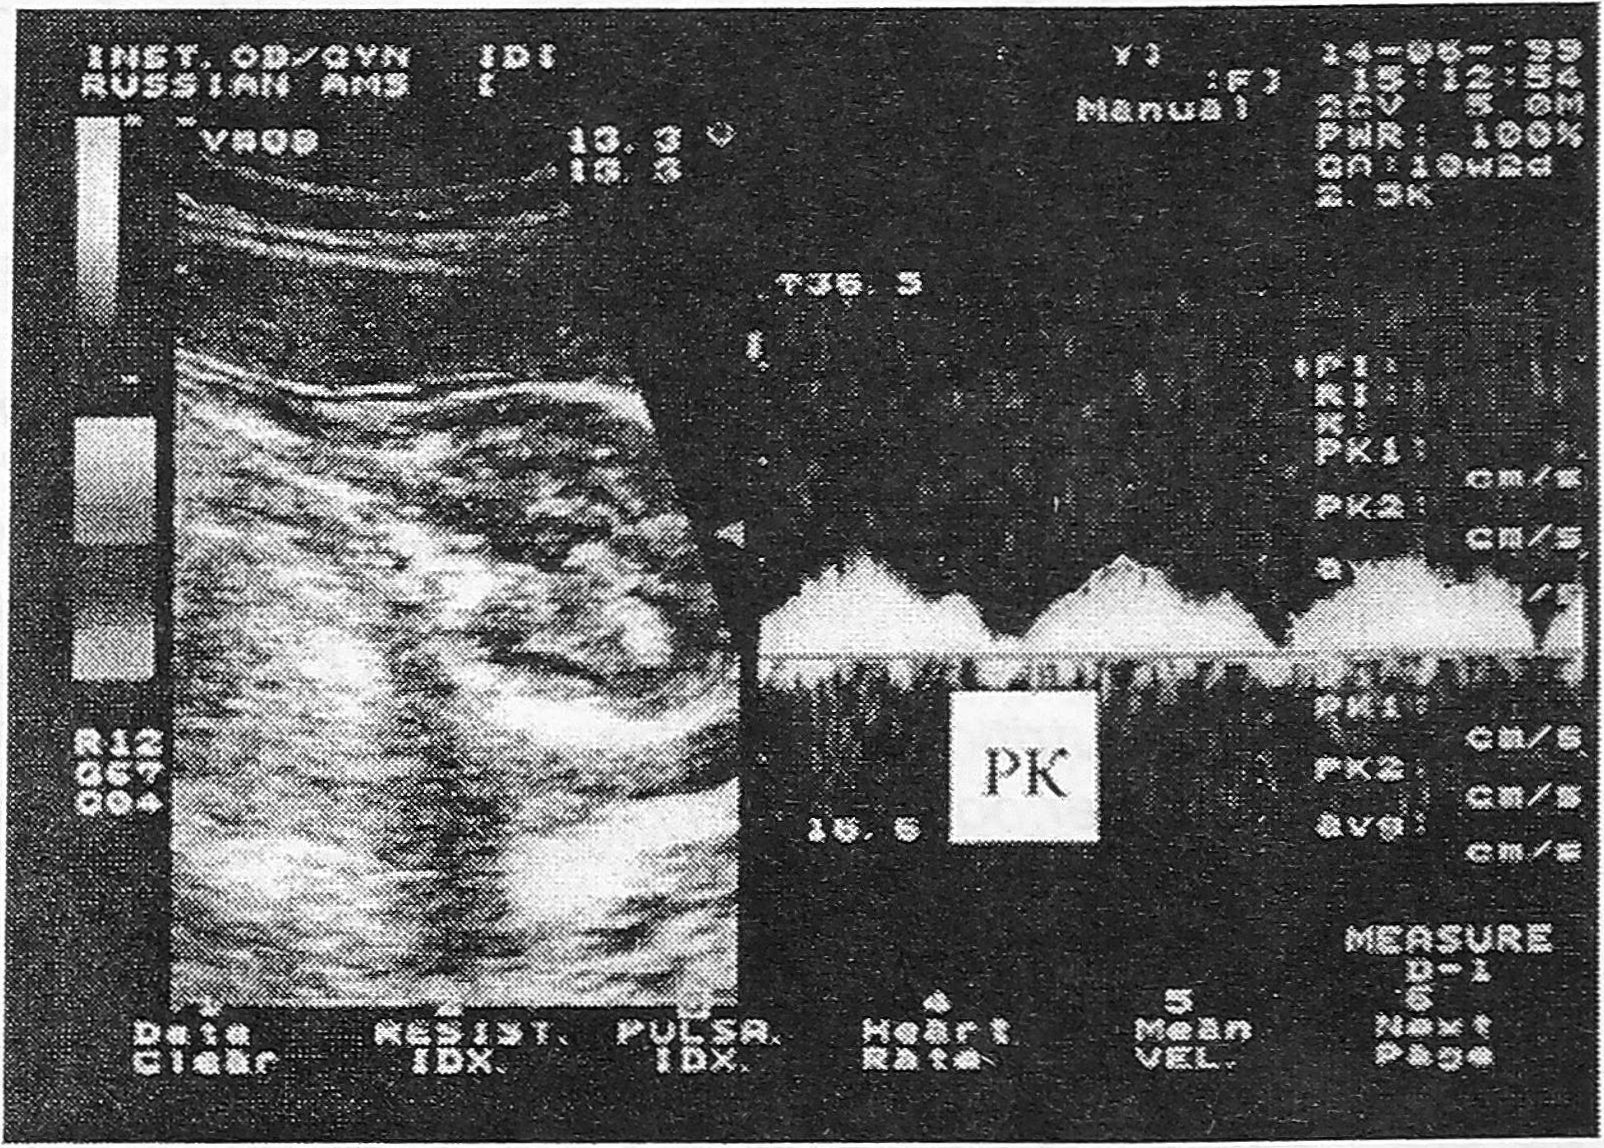

Согласно результатам нашего исследования основные изменения кровотока в вене пуповины наблюдаются в течение первого и начале второго триместра беременности. Процесс его формирования включает несколько этапов, которые характеризуются сменой условий циркуляции крови в пупочной вене. При этом процессы становления кровотока в пупочной вене совпадают с периодом формирования низкорезистивных плацентарных сосудов. Так, в первом триместре беременности в пупочной вене определяется пульсирующий кровоток, обусловленный влиянием работы сердца плода (рис.3). В начале второго триместра пульсация в пупочной вене постепенно исчезает. После 16-й недели беременности оксигенированная кровь из плаценты к плоду поступает с постоянной скоростью, что свидетельствует о переходе на качественно новый уровень становления пуповинной циркуляции.

Рис. 3. Допплерограмма пульсирующего кровотока в вене. Д — максимальная скорость кровотока, Е - минимальная скорость кровотока.

Постоянный спектр кровотока в пупочной вене является важным критерием стабильности гемодинамических процессов в фетоплацентарной системе во второй половине нормально развивающейся беременности.